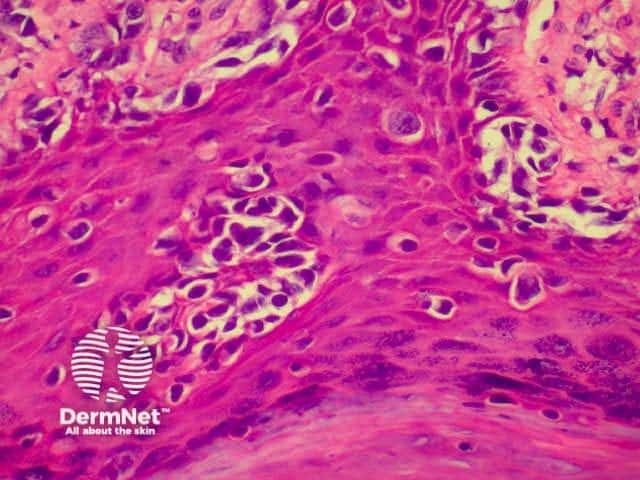

SCC is characterised by proliferation of irregular nests of abnormal squamous cells arising from the epidermis and invading the dermis. Tumours are traditionally divided into well, moderately or poorly differentiated tumours by a subjective assessment of how significantly the tumour cells differ from normal keratinocytes. In general, the greater the degree of keratinization, the better differentiated the tumour is thought to be. Except in the case of very poorly differentiated tumours, this does not have a great bearing on prognosis. More important is the depth and irregularity of invasion, particularly the presence of perineural infiltration, which is associated with a much higher rate of recurrence if not widely excised. The site of the lesion is also important; tumours of the lips and ears have a considerably higher rate of metastasis to lymph nodes.

From the above comments it can be seen that the histological features of SCCs can vary, but in general are:

Pathology of SCC Pathology of SCC Pathology of SCC Pathology of SCC